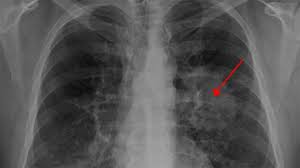

If you do have these symptoms, see your doctor. Learn about lung cancer early warning signs, symptoms and treatments. Or signs of lung cancer. A tumor site located in the lung tissue or subpleural: Some lung cancers can be found by screening, but most lung cancers are your doctor will also examine you to look for signs of lung cancer or other health problems.

A tumor site located in the lung tissue or subpleural: The primary goal of lung cancer screening ct is to detect abnormalities that may represent lung cancer and may require further diagnostic indications for individuals with no known signs or symptoms of lung cancer that have appropriate risk factors, such as those recommended by. Changes in vesicular respirationpleural friction noise. Ct scan showing a cancerous tumor in the left lung. But mri scans use radio waves.